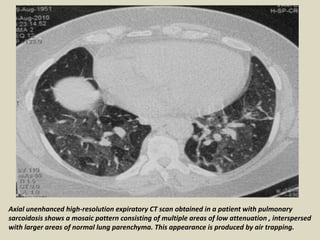

AIRWAY INVOLVEMENT The most common imaging findings

of airway involvement are a mosaic attenuation pattern, air

trapping, tracheobronchial abnormalities and atelectasis.

Mosaic Attenuation Pattern: It refers to the presence of

heterogeneous attenuation in the lung parenchyma on

inspiratory CT images. In patients with sarcoidosis, this pattern

results from airway involvement by granulomas or fibrosis,

which may lead to obstruction.

Air trapping: It is characterized by focal areas of decreased

attenuation on expiratory CT images. It is a common, albeit

nonspecific, feature. There is no correlation with the stage of

the disease.

Axial unenhanced high-resolution expiratory CT scan obtained in a patient with pulmonary

sarcoidosis shows a mosaic pattern consisting of multiple areas of low attenuation , interspersed

with larger areas of normal lung parenchyma. This appearance is produced by air trapping.